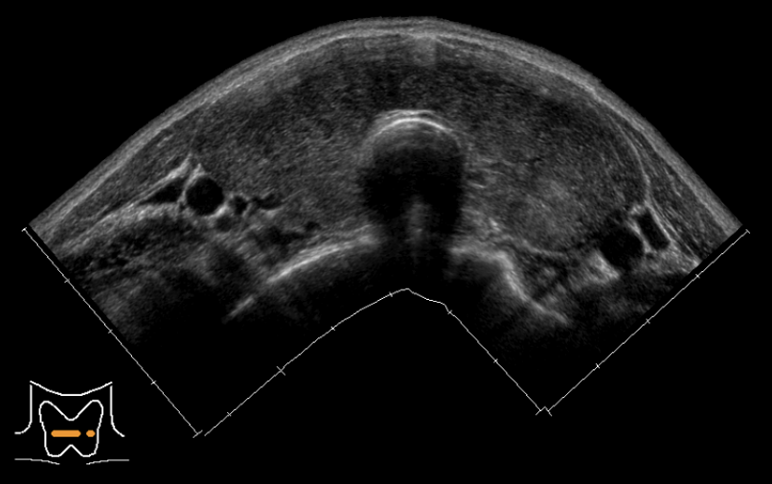

バセドウ病

甲状腺全体が腫れて大きくなり、血流が多くなります。

※軽症の場合は正常な甲状腺とほとんど変わらない場合もあります。